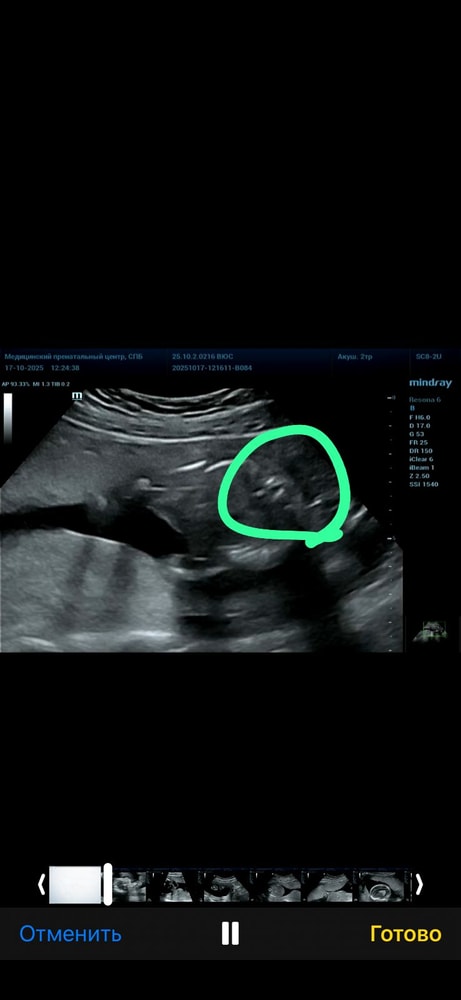

Анализы, скринингиВот и сделала я второй скрининг, получила видео с узи, когда смотрела узи (доктор не разу не выключал экран) то по видео поняла, что мальчик 🤣 нам дали конвертик с полом, на котором уже было все напечатано (не от руки) и запечатан с двух сторон, переживаю была ли ошибка в конверте. Я вижу мальчика 🤣 а на конверте девочка. У меня есть два сына и я уже боюсь узи 🤣

срок беременности 19 недель и 5 дней